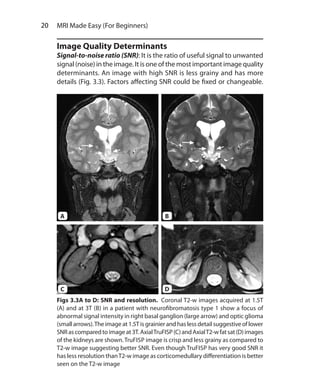

Signal-to-noise ratio (SNR): It is the ratio of useful signal to unwanted

signal (noise) in the image. It is one of the most important image quality

determinants. An image with high SNR is less grainy and has more

details (Fig. 3.3). Factors affecting SNR could be fixed or changeable.

Figs 3.3A to D: SNR and resolution. Coronal T2-w images acquired at 1.5T

(A) and at 3T (B) in a patient with neurofibromatosis type 1 show a focus of

abnormal signal intensity in right basal ganglion (large arrow) and optic glioma

(smallarrows).The imageat 1.5Tisgrainierandhaslessdetailsuggestiveoflower

SNRascomparedtoimageat3T.AxialTruFISP(C)andAxialT2-wfatsat(D)images

of the kidneys are shown.TruFISP image is crisp and less grainy as compared to

T2-w image suggesting better SNR. Even though TruFISP has very good SNR it

has less resolution thanT2-w image as corticomedullary differentiation is better

seen on the T2-w image